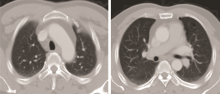

患者男性、51岁, 因“ 涕血3个月” 入院。2010年8月胸部CT检查诊断双肺转移瘤(图1)。2010-09-10我院鼻咽部CT检查示:鼻咽肿物侵犯咽旁间隙、颅底、蝶窦, 伴右颈淋巴结转移(图2); 鼻咽镜行鼻咽肿物活检病理示:鼻咽低分化鳞状细胞癌。诊断为鼻咽低分化鳞状细胞癌cT3N1M1(双肺) Ⅳ c期(AJCC 2010), PS=1。2010-09-21至2011-01-12予TPF方案化疗6周期, 其中紫杉醇256 mg d1、DDP 30 mg d1~d5、5FU 950 mg d1~d5。2周期后(2010-11-04)复查胸部和鼻咽CT示:鼻咽肿物明显缩小, 左上肺前段小结节, 性质待定(图3)。鼻咽部病灶部分缓解(partial remission, PR), 肺部病灶PR, 总评价PR; 4周期后(2010-12-20)复查胸部CT示, 左肺上叶前段纤维灶; 右肺下叶炎性改变, 左肺上叶轻度肺气肿, 肺大泡形成(图4)。4周期后鼻咽病灶PR, 肺部病灶完全缓解(complete remission, CR), 总评价:PR; 6周期后(2011-02-24)复查胸部CT示:双肺多发小结节, 考虑转移瘤可能性大; 肺气肿, 左肺上叶肺大泡形成。鼻咽病灶较前进一步缩小(图5)。6周期后鼻咽病灶PR, 肺部病灶进展(progressive disease, PD), 总评价:PD。

张奕(放射科医师):基于患者的病史和外院CT片, 结合该患者2月份到4月份治疗后复查的情况, 因为该患者肺部的转移瘤在缩小中, 4月份的片中瘤灶基本上消失了, 左上肺有一些囊泡状的空泡影, 考虑为肺气肿(图6)。肺内血行转移小结节有以下三方面的特点:①膨胀性生长, 形态比较饱满, ②多呈类圆形, 边缘比较光滑, ③较少侵犯胸膜。根据以上的特点, 我重新回顾了患者2011年2月的CT片, 逐个小结节分析后认为:左下肺的结节是贴着胸膜塌陷式生长的, 形态不太饱满, 边界也不太光滑。右中肺的几个结节的毛刺非常发达(图7), 意识到以前的诊断有些不对。从图中我们可以清晰地看到, 结节不是特别圆, 边缘不光滑, 形态不饱满, 有塌陷, 有些有毛刺。那么这些小结节是否为转移灶?从影像学上来说, 有以下几点支持转移:①多发小结节, ②肿瘤病史; 以下几点不支持转移:①多处病灶位于胸膜处, 并有牵拉征象, ②多处病灶可见长毛刺, ③多处病灶可见塌陷, 形态欠饱满。至此我们认为, 2月份新发病灶的影像诊断应该是炎性肉芽肿。我们的诊断前后不同, 说明我们对病史的了解和图像的观察不够深入。图8是比较典型的炎性肉芽肿(A、B)和转移瘤病灶(C、D)的CT图像。